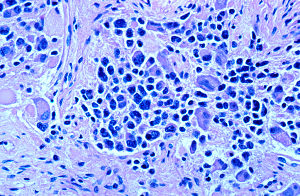

Neuroblastom-Zellen: Immuntherapie verbessert die Chancen (Foto: Wikimedia) |